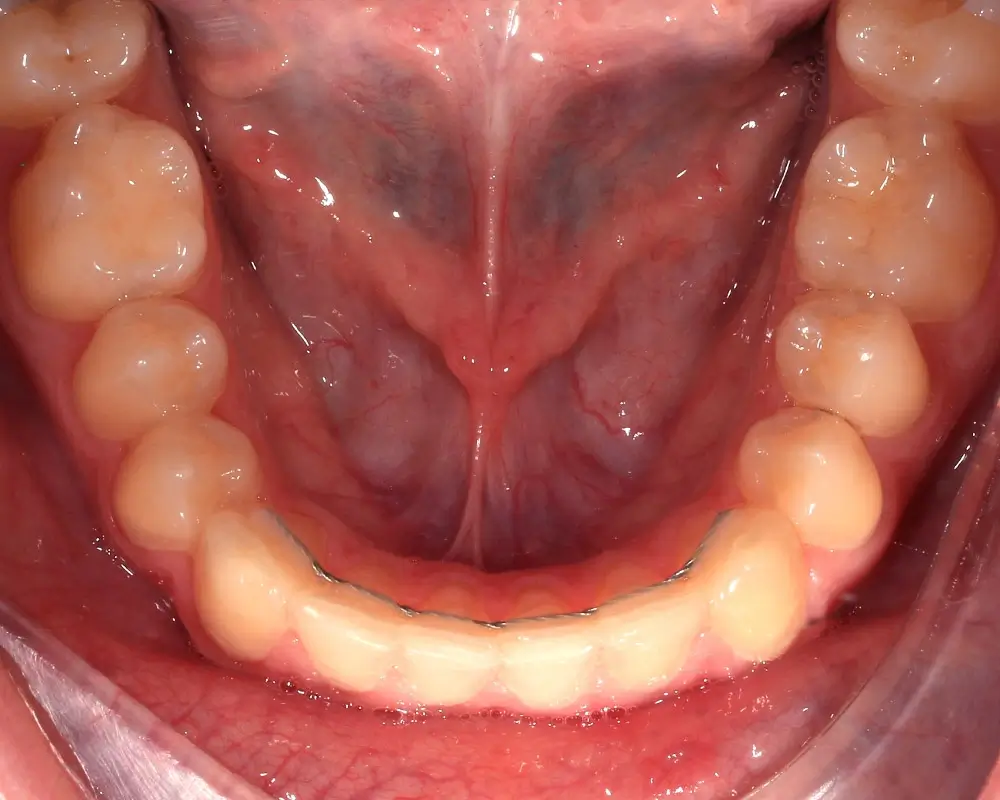

Скученность - Кейс 25

Эффективность устранения дефекта прикуса посредством элайнеров FlexiLigner.

16

Количество кап НЧ

Результаты лечения